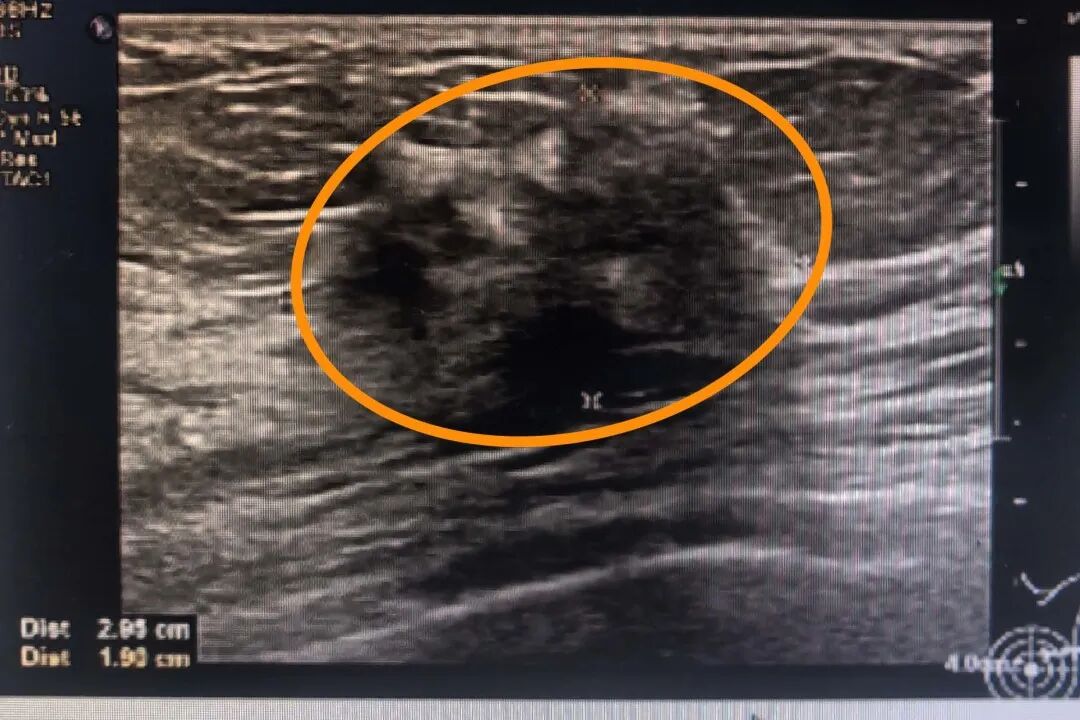

檢查的過程中,醫(yī)生對(duì)張女士的病情有了新發(fā)現(xiàn),并非只有一個(gè)病灶,而是在可觸及腫塊的周圍還有一個(gè)小的病灶。彩超顯示張女士左乳2點(diǎn)鐘方向可見一30×19×29mm的低回聲結(jié)節(jié),邊界不清,形態(tài)不規(guī)整,周邊有血流;另于左乳4點(diǎn)方向可見一8.3×7.7mm的低回聲結(jié)節(jié),邊界不清,形態(tài)不規(guī)整,周邊有血流。